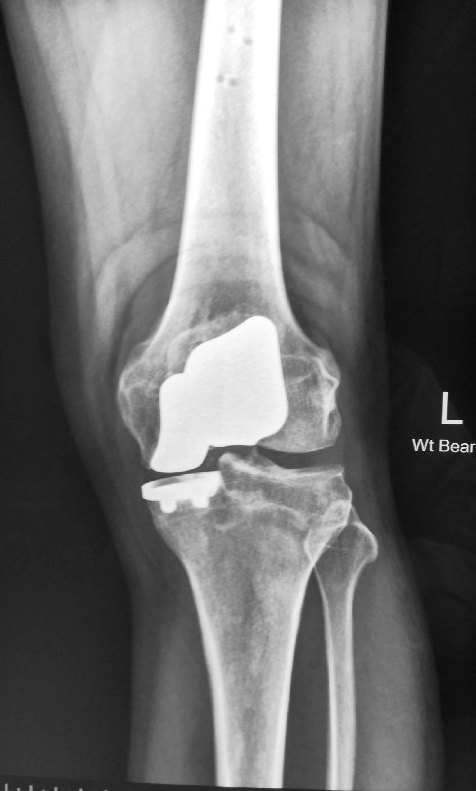

X-rays showed mild narrowing of the medial compartment of his left knee. In addition, there was an obvious severe osteoarthritis of the patellofemoral joint (kneecap joint).

Post-operative check x-rays showed excellent alignment of the implants.